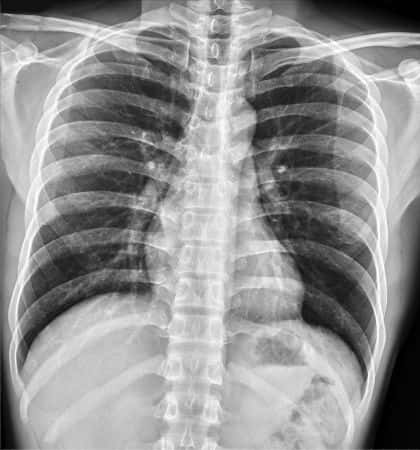

This case involves a thirty-five-year-old female who presented to her neurologist with difficulties swallowing. Her past medical history included myasthenia gravis and hypertension. She first established care with her neurologist when she was diagnosed with myasthenia gravis, an autoimmune neuromuscular disease. Based on these findings, the neurologist believed that she experienced an exacerbation of myasthenia gravis. He increased the dosage of her medication, pyridostigmine, despite the fact that she was not having any other symptoms. He then scheduled her for a one-month, follow-up appointment. Over the next month, she developed chest pain, shortness of breath, cough, and facial plethora which caused her to go to the hospital. At the ER, a CT scan was performed which revealed an anterior mediastinal mass. Biopsy confirmed that the woman had a stage III thymoma and was scheduled for a thymectomy. After surgery, she required months of radiotherapy and chemotherapy. One of the chemotherapy agents used to treat her condition was doxorubicin. Six months after chemotherapy, the woman’s ejection fraction was 25%. She was diagnosed with a dilated cardiomyopathy secondary to doxorubicin therapy. Between receiving chemotherapy for her thymoma and managing her cardiomyopathy, the patient experienced prolonged hospitalizations and pain.

The neurologist, in this case, did not identify a condition that is seen in 10--15% of patients with myasthenia gravis (MG). Instead, he thought that she was experiencing symptoms of MG and increased her medication dosage. Thymoma is an epithelial cell tumor of the thymus located in the anterior mediastinum. Due to its location, a thymoma can present as difficulties swallowing due to compression of the esophagus. It can also compress the superior vena cava causing dyspnea, headache, edema, venous distention, lightheadedness, cough, and facial redness. Thymoma is also associated with pure red cell aplasia and other autoimmune diseases. Thymoma is typically diagnosed with a CT scan, which reveals a lesion in the anterior mediastinum. Needle biopsy is also performed under CT guidance. Laboratory work can assist with the diagnosis using a full blood count, protein electrophoresis, electrolytes, liver enzymes, and renal function. Surgery is the most successful intervention for a thymoma. For all stages, a thymectomy should be performed. Stage III and IV disease may also require radiotherapy and chemotherapy. A common chemotherapeutic used to treat thymoma is doxorubicin. Dilated cardiomyopathy is a major side effect of doxorubicin use. Had the diagnosis been made earlier during stage I or II, she would not have required chemotherapy.